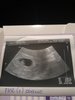

Na fb, grupie Karoliny - Daria Gertner. Więc po wizycie : wychodzi termin z @ na 06.07 aczkolwiek wg @ powinnam być w 8tc, a wg pomiarów wychodzi 6+3 więc termin się napewno zmieni 😍 Serduszko bije, dostałam L4 leżące do następnej wizyty 09.12. Dodatkowo mam brać luteinę nie raz jak do tej pory, a dwa razy dziennie i magneB6 3x dziennie. Do tego witaminki i dieta. Ciśnienie idealne, szyjka i macica w stanie idealnym 😍